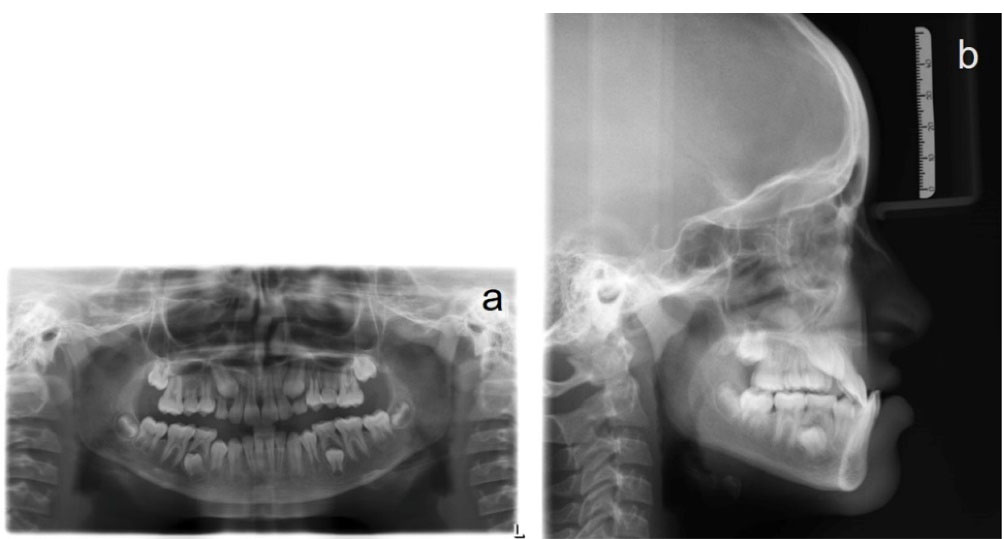

A panoramic radiograph, taken at the early permanent dentition stage of development, did not reveal any bony or periodontal abnormalities (). Cephalometric analysis revealed a skeletal Cl III anteroposterior relationship (ANB, -6°; Wits appraisal, -8 mm), a retrognathic maxilla (SNA, 76°), a prognathic mandible (SNB, 82°), and a hypodivergent growth pattern. A large maxillomandibular discrepancy with Co-A to Co-Gn of 26 mm was noted (the normal range is 20‒23 mm). The maxillary incisors were slightly proclined (U1 to SN, 105°), whereas mandibular incisors had normal inclinations (IMPA, 89°) (; Table 1). The soft tissue analysis confirmed upper lip retrusion and lower lip protrusion. The patient was in the CS3 stage of skeletal maturation, according to the CVMI method.

Figure 2.

Pretreatment radiographs. (a) Panoramic radiograph, (b) Lateral cephalogram.